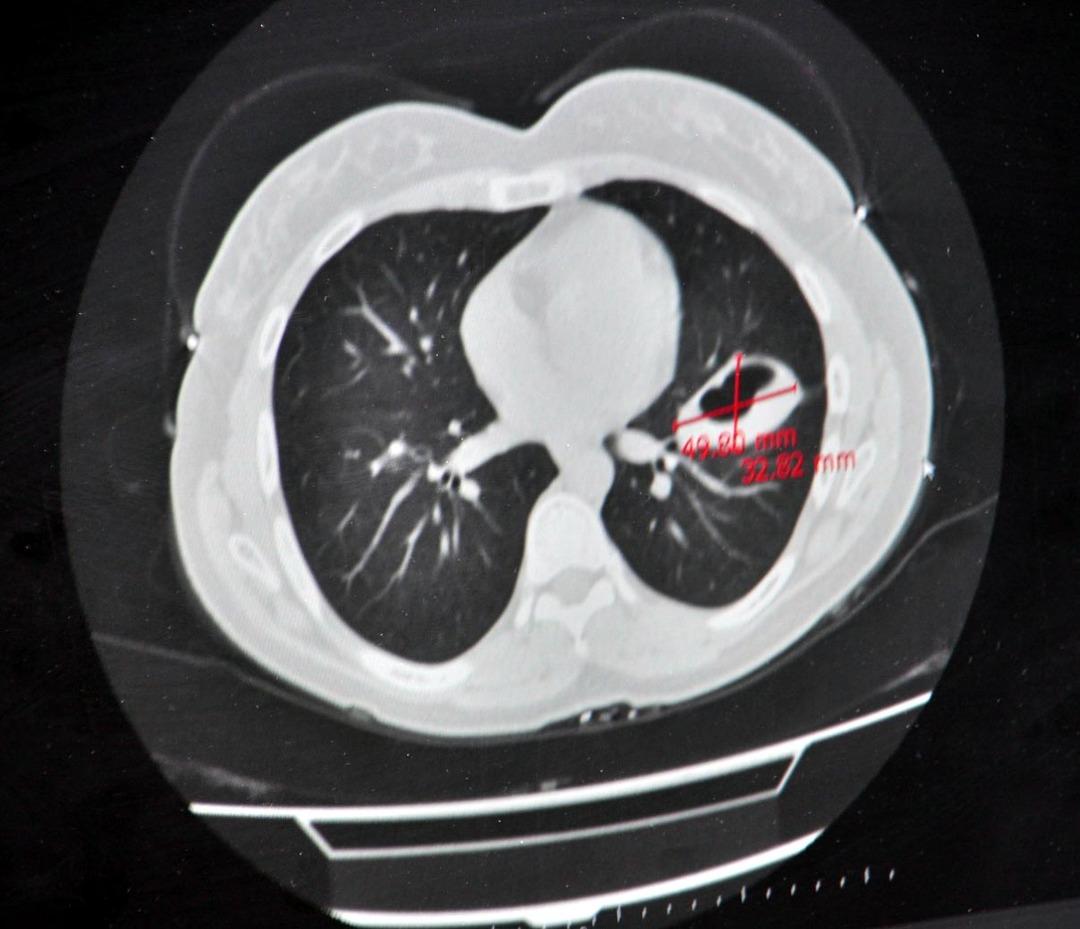

“Kistler karaciğer ve akciğerlerde daha yaygın olarak görülür”

Perintcek, hastalığın kistin küçük olduğu dönemde yıllarca belirtilmeden bakabileceğini söyledi. Kusma ve bazen kaşıntı kalplerin kalbinin kalbinde görülebilir. Kist patladığında alerjik reaksiyonlar meydana gelebilir.